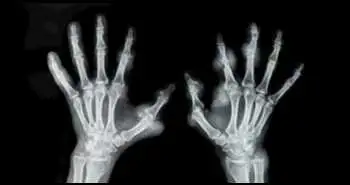

Эффективность терапии сарилумабом в течение 5 лет у пациентов с ревматоидным артритом, не поддающимся лечению ингибиторами ФНО

Применение сарилумаба у пациентов с ревматоидным артритом (РА), не поддающимся лечению ингибиторами ФНО, может обеспечить достижение долговременной клинической эффективности.

В ходе исследования, проведенного Roy Fleischmann и соавт., установлено, что применение сарилумаба (человеческого моноклонального антитела) у пациентов с РА, не поддающимся лечению ингибиторами ФНО, обеспечивает достижение стойкой эффективности в течение 5 лет.

Пациенты с РА, получавшие плацебо или сарилумаб в дозе 150 мг или 200 мг 1 р/2 нед в сочетании с терапией стандартными синтетическими базисными противоревматическими препаратами (ссБПРП) в исследовании TARGET длительностью 24 недели, могли быть включены в долгосрочное открытое дополнительное исследование (ОДИ) на получение сарилумаба в дозе 200 мг каждые 14 дней в комбинации с терапией ссБПРП. Снижение дозы в ОДИ до 150 мг 1 р/2 нед допускалось по решению исследователей или по соображениям безопасности согласно протоколу.

В ОДИ приняли участие 454 из 546 пациентов (83 %), получавших сарилумаб. Общий период исследования составил 1654,8 пациенто-года, при этом 268 пациентов (51 %) получали терапию в течение более 4 лет. Частота развития нежелательных явлений (НЯ), частота прекращения лечения из-за развития НЯ и частота развития инфекции на 100 пациенто-лет составили 160,4, 8,1 и 57,8 соответственно. Наиболее частым НЯ была нейтропения. У 74 пациентов (14,2 %) общее количество нейтрофилов было < 1000 клеток/мм3, и у 48 пациентов, получавших терапию сарилумабом, количество нейтрофилов удалось нормализовать. По результатам последующего наблюдения в течение 5 лет была доказана стойкая клиническая эффективность терапии. Эффективность терапии у пациентов с ревматоидным артритом, не поддающимся лечению иФНО, у пациентов, продолжавших принимать препарат в дозе 200 мг либо снизивших дозу до 150 мг, была сопоставима.